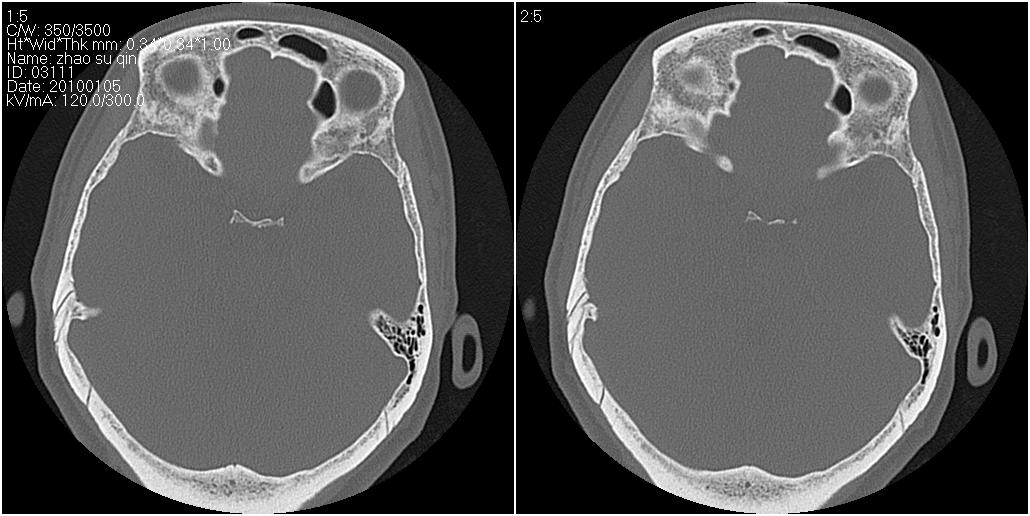

标题: CT24015:一个头部外伤患者进行鉴定,除了左侧筛板骨折,哪 [打印本页]

标题: CT24015:一个头部外伤患者进行鉴定,除了左侧筛板骨折,哪

1)左侧筛板骨折。2)双侧筛窦炎症(或积血)。

请明示骨折部位。